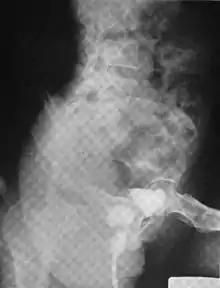

Urethral diverticulum is often an incidental finding.[2] It can be diagnosed using magnetic resonance imaging and/or micturating cystourethrography.[1] Other studies that can be used to diagnose urethral diverticulum include intravenous urography, urethroscopy, and/or ultrasound. Conditions that should be distinguished from urethral diverticulum in a differential diagnosis include overactive bladder, Gartner's duct cyst, Gartner's duct abscess, ectopic caeco-ureterocele, interstitial cystitis, pelvic inflammatory disease, endometriosis, and cancer.[3]